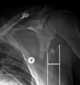

Congenitally abnormal scapula

Sprengel's deformity (also known as high scapula or congenital high scapula) is a rare congenital skeletal abnormality where a person has one shoulder blade that sits higher on the back than the other. The deformity is due to a failure in early fetal development where the shoulder fails to descend properly from the neck to its final position. [Source: Wikipedia ]